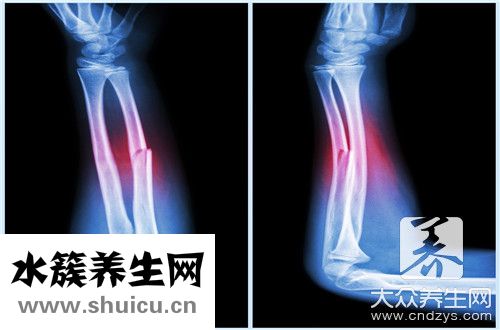

你可能聽過這樣的話,傷筋動骨一百天。 人在做某事時意外傷害自己,就會骨折,扭傷腳。 面對這些情況,你需要好好利用時間調(diào)整自己的身體。 人們通常花一百天的時間休養(yǎng)。 那么,讓我們詳細介紹一下為什么...